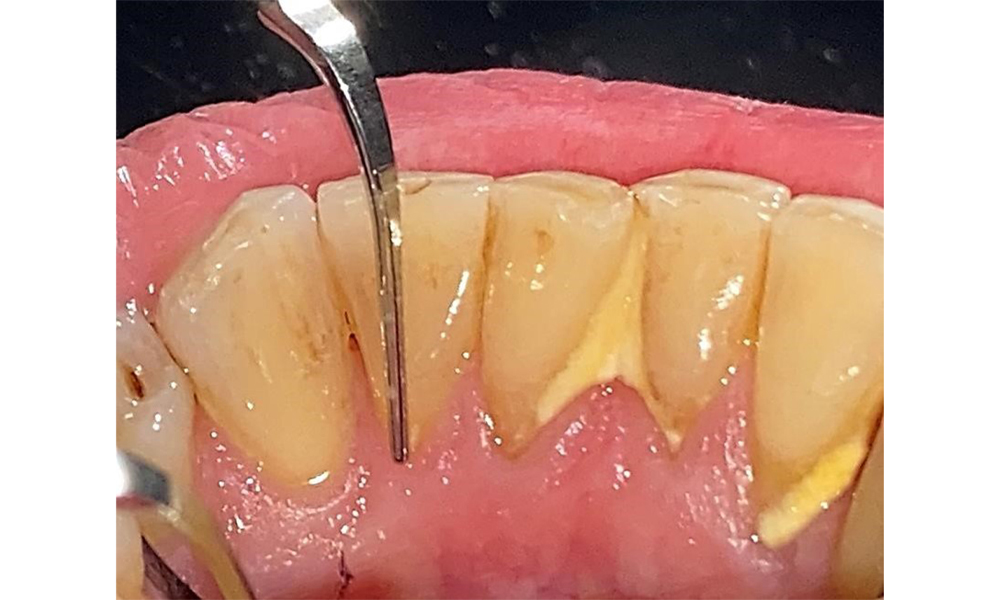

There are no limitations regarding the choice of instrumentation methods. Regular supragingival and subgingival instrumentation is essential to prevent disease progression due to the pre-existing periodontitis and high risk of recurrence. There are no limitations placed on the selection of instruments for mechanical biofilm removal from a general medical perspective, and removal should be performed as needed. Hard and mineralized plaque, such as calculus and concretions, should be removed using manual instruments or sonic/ultrasonic scalers (Fig. 9) (8, 9).

Use an ultrasonic tip to remove hard, mineralized plaque (Proxeo Ultra scaler with the Perio tip, W&H, shown here). © Dr R. Krapf

Fig. 9: Use an ultrasonic tip to remove hard, mineralized plaque (Proxeo Ultra scaler with the Perio tip, W&H, shown here). © Dr R. Krapf

Supragingival and subgingival biofilm removal is indispensable for maintaining the stability of the periodontal condition. Air polishing using low-abrasive powder is suitable for this purpose. Periodontal pockets and exposed root surfaces must be cleaned with low-abrasion powders. The use of a flexible parotip is recommended for patients with increased probing depths (deeper than 5 mm) (Fig. 10). (9)